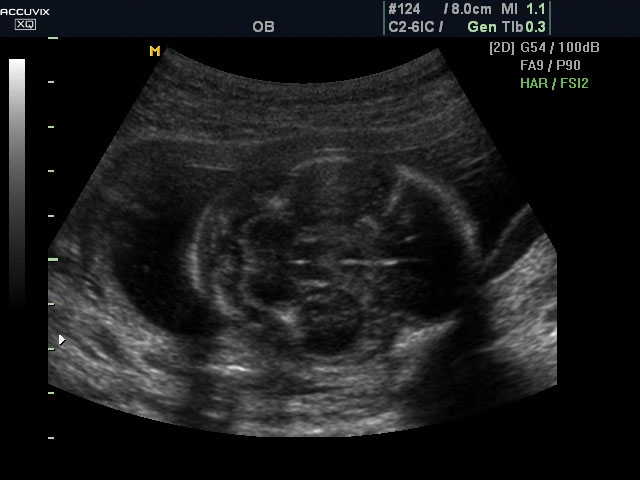

A pontos analízis és diagnózis iránti egyre növekvő igény kiszolgálására a MEDISON egy új real time képfeldolgozó technológiát fejlesztett ki Dynamic MR™ elnevezéssel. Az eljárás a diagnosztikus ismeretanyagot a precizitás és a pontosság egy teljesen új szintjére emeli. Használata az alapvető 2D ultrahang képinformáció real time, kivételesen kristálytiszta és kiemelkedően részletezett megjelenítését teszi lehetővé tűéles kontúrok és finoman rajzolt szövetstruktúra mellett. A DMR™  technológia ideális eszköze az ultrahang-diagnosztikának kezdve a szülészet-nőgyógyászattól a foetalis echon át az általános alkalmazásokig.

Magzati koponya képe normál 2D módbanMagzati koponya 2D képe bekapcsolt Dynamic MR funkcióvalMagzat törzsének képe normál 2D módbanMagzat törzsének képe bekapcsolt Dynamic MR funkcióvalMagzat felsőajakjának és orrának képeMagzat felsőajakjának és orrának képe bekapcsolt Dynamic MR funkcióval

A DynamicMR alkalmazása az átlagos ultrahang teljesítményt a zaj és szemcsézettség jellegű műtermékek kiszűrése révén a vizuális diagnosztika, a precizitás és a pontosság új szférájába emeli. Figyelje meg a cerebellum, CSP és cisterna magna élstruktúráit, mennyire pontosan definiáltak és a teljes agyi struktúra ábrázolása a Dynamic MR alkalmazásával milyen látványosan javul.